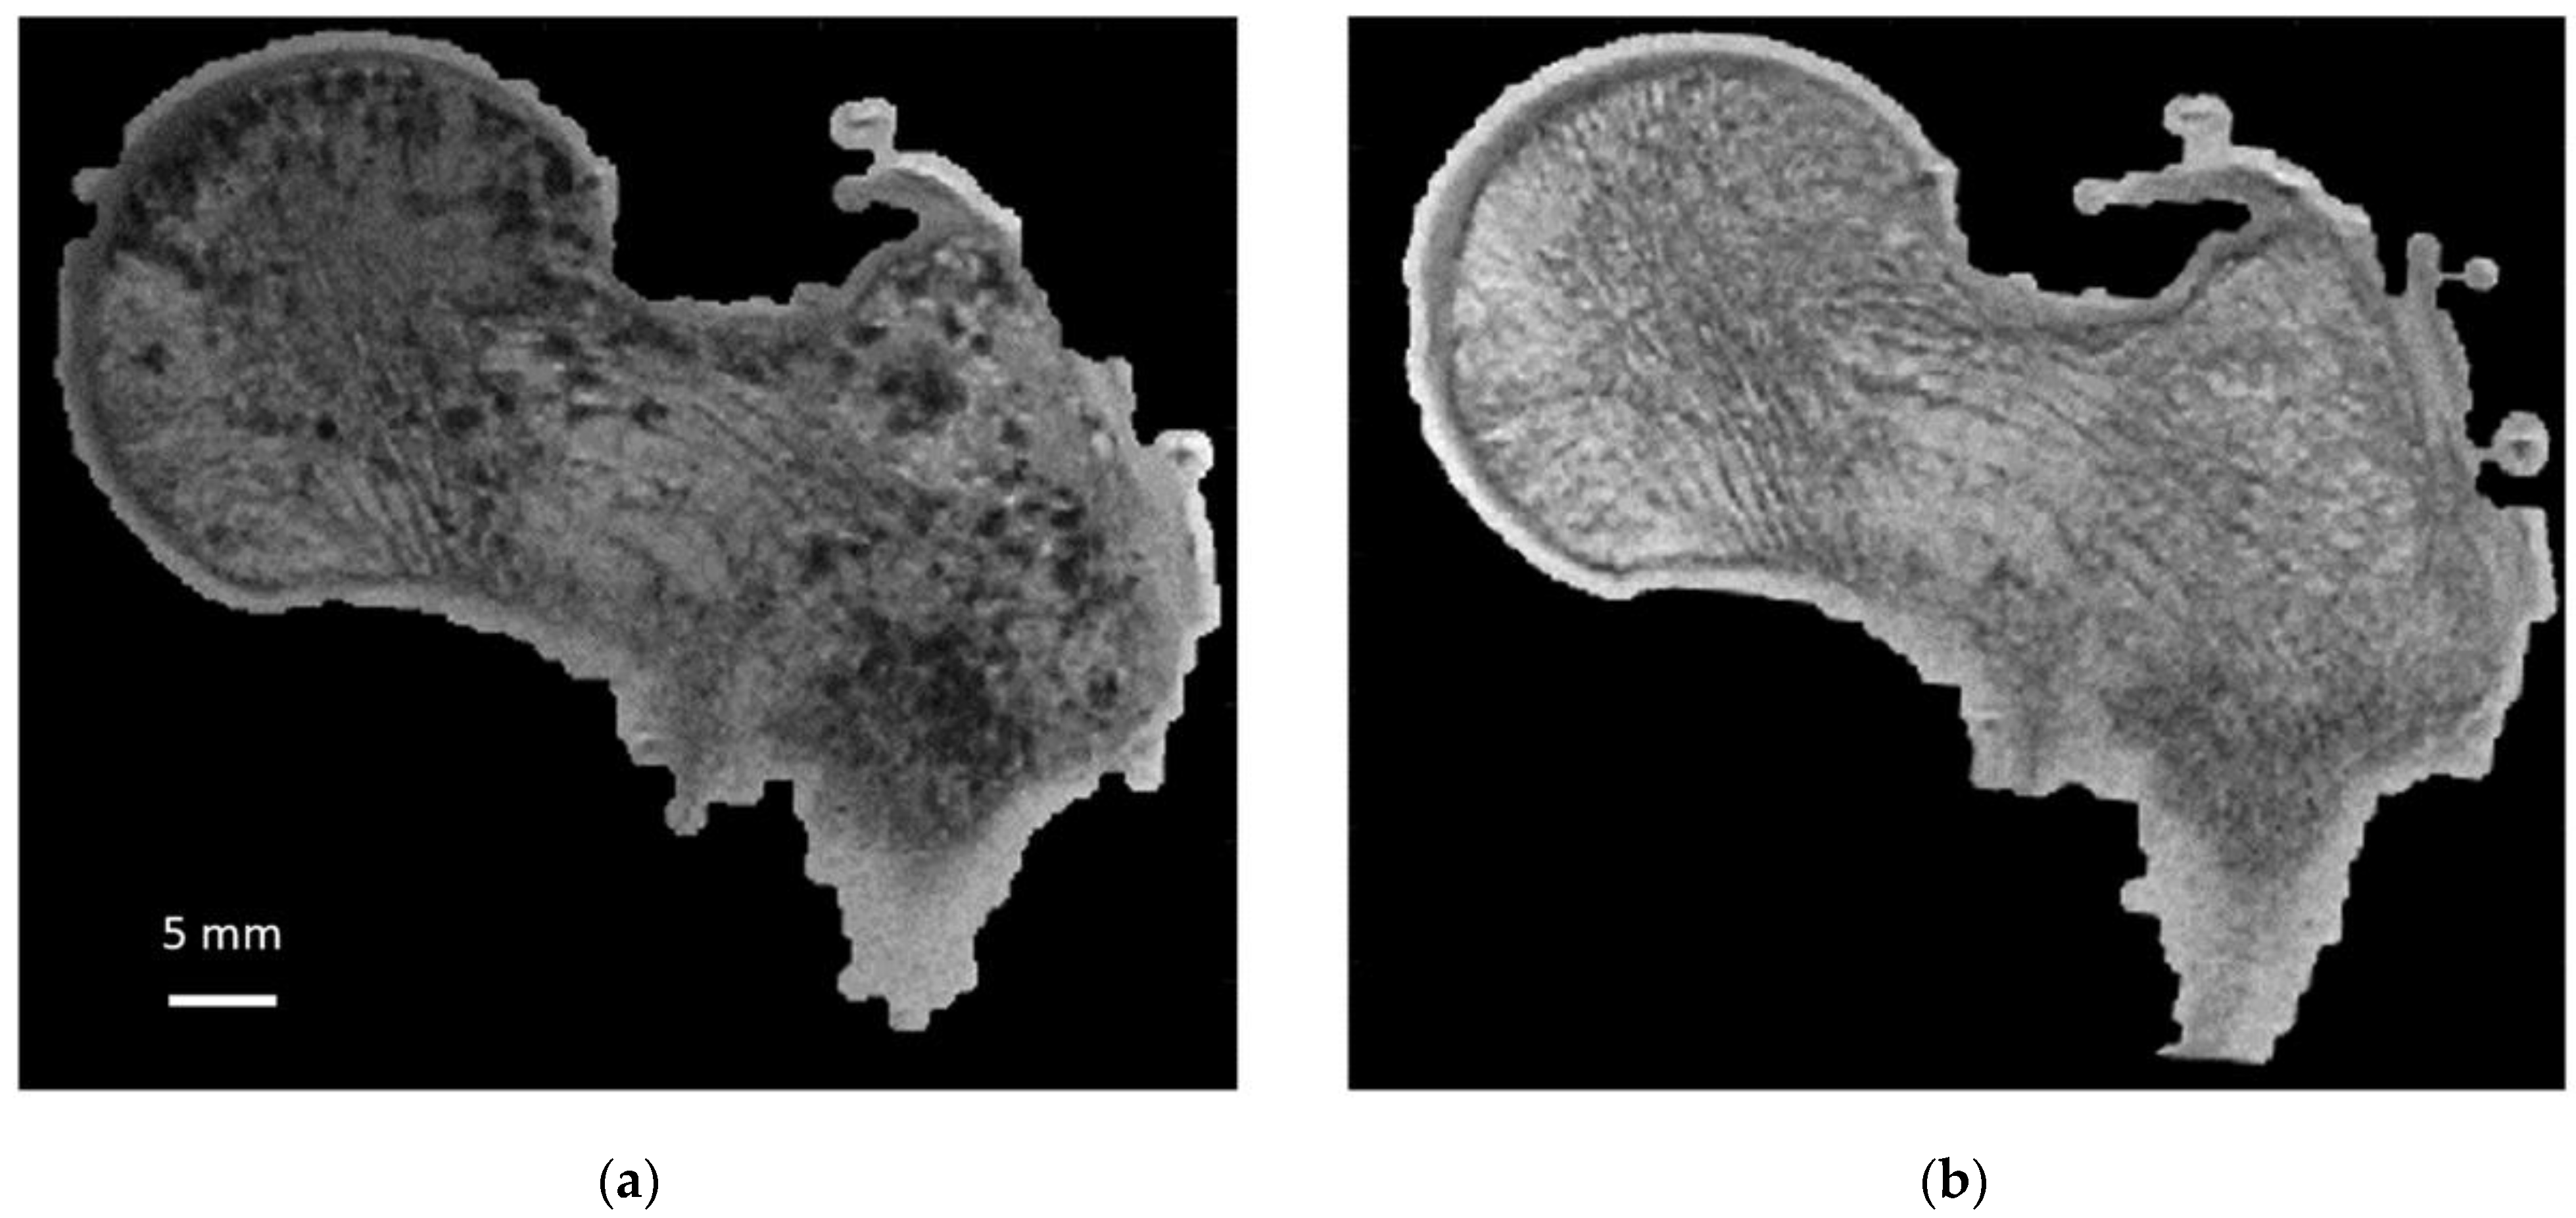

Figure 1. Sample 1: same coronal plane before and after bubble removal. Sample 1 (S1): same coronal plane for 3T MRI images (0.21 × 0.21 × 1.1 mm) before (a) and after (b) application of air bubble reduction protocol.

As illustrated in Figure 6, air bubbles were clearly visible as darker pixels in the μCT images. The corresponding air volume present inside S1 was 12.4 cm3 (Table 1). During the vacuum procedure, the movement of air bubbles from the bottom cross-section was clearly visible. Three vacuum cycles were applied, and the total amount of air bubbles still present in the bone microstructure was greatly reduced (<0.5%) of the total bone marrow volume (Table 1). Moreover, the residual amount of air bubbles after each vacuum cycle was evaluated in the case of S1. The results showed that the first vacuum cycle led to a significantly large reduction (98.8%) in air volume, while the remaining air volume was completely removed after two additional cycles (Figure 6 and Table 1).

To quantify the bone microstructure obtained by MRI, a comparison with that obtained from X-ray microtomography is necessary. Moreover, we propose to conduct this study on large cadaveric human bones since MRI and microtomography allow us to image them in their totality at the respective maximum resolution. However, MRI scanning of cadaveric bones suffers from the occurrence of image artifacts due to the presence of air bubbles that may be introduced during sample cutting or signal voids created by the decomposition process that could be misclassified as “bone” signal [4,15]. In addition, air inclusions cause magnetic susceptibility artifacts, leading to overestimation of bubble size and artificial broadening of trabecular bone thickness during MRI acquisition (Figure 1). Therefore, ex vivo MRI can only be performed if air inclusions in the marrow space are removed and replaced given that air-bubble-related artifacts would lead to overestimations of microarchitecture metrics. Very few methods have been developed so far to handle this issue. Bone marrow removal using a gentle water jet has been reported and combined with centrifugation in order to remove air bubbles trapped in the marrow spaces [1,15,16,17]. However, this method is poorly suited for whole bone segments and has been usually applied on small trabecular samples. Moreover, mechanical properties of the femur structure are affected given that dry and hydrated bones are known to have different biomechanical properties [18,19]. In that context, biomechanical tests would be biased. Samples freezing may limit tissue decomposition, which is a source of air bubble generation. However, it has been reported that MR images of unfrozen samples are characterized by a substantially lower signal-to-noise ratio [4] and a poor contrast between bone and background such that image segmentation can also be compromised [4].